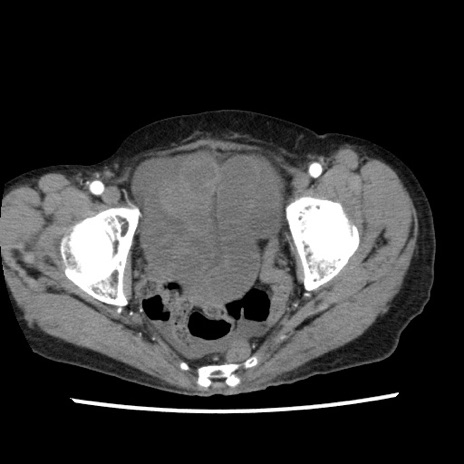

症例1(横断像)

【症例】80歳代女性

【主訴】腹痛

【現病歴】8時間前から腹痛あり来院。

【既往歴】糖尿病、脂質異常症、子宮体癌にて子宮全摘術

【身体所見】意識清明・会話良好だが腹痛で苦悶様、全腹部にわたって反跳痛と圧痛あり

【データ】WBC 13600、CRP 0.14、LDH 224、CK 90